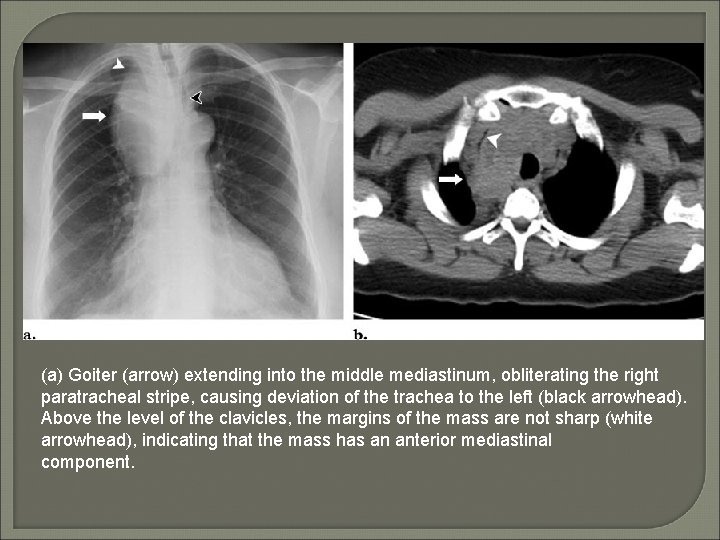

(a) Goiter (arrow) extending into the middle mediastinum, obliterating the right paratracheal stripe, causing deviation of the trachea to the left (black arrowhead). Above the level of the clavicles, the margins of the mass are not sharp (white arrowhead), indicating that the mass has an anterior mediastinal component.